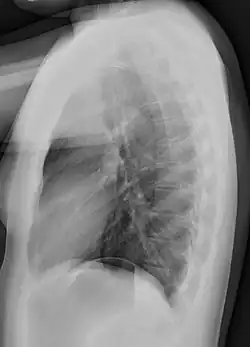

Normal lateral chest radiograph.

Lateral views of the chest are obtained in a similar fashion as the posteroanterior views, except in the lateral view, the patient stands with both arms raised and the left side of the chest pressed against a flat surface.